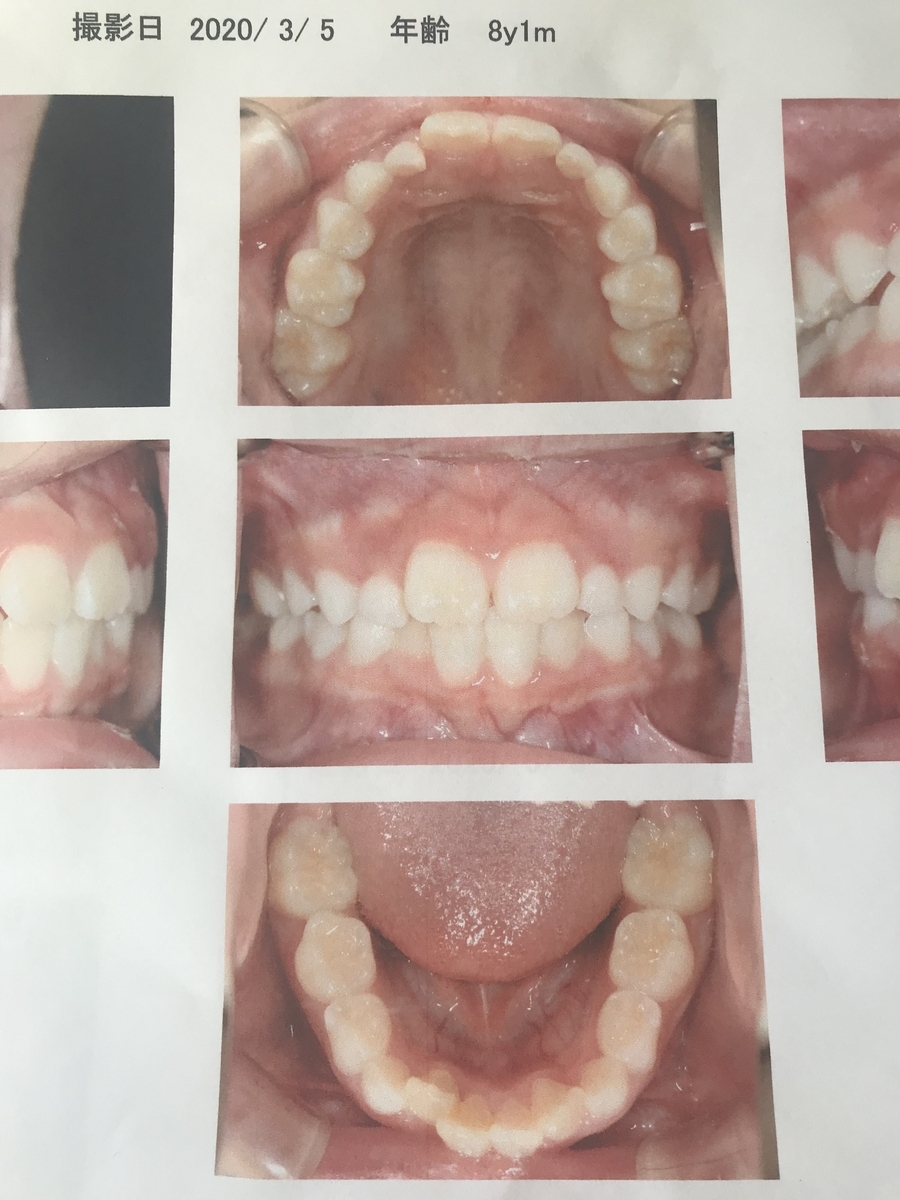

2020年3月(2年生)

治療前、上2本下4本が永久歯に生え変わっていますが、既に下の歯が内側に入っていってます。